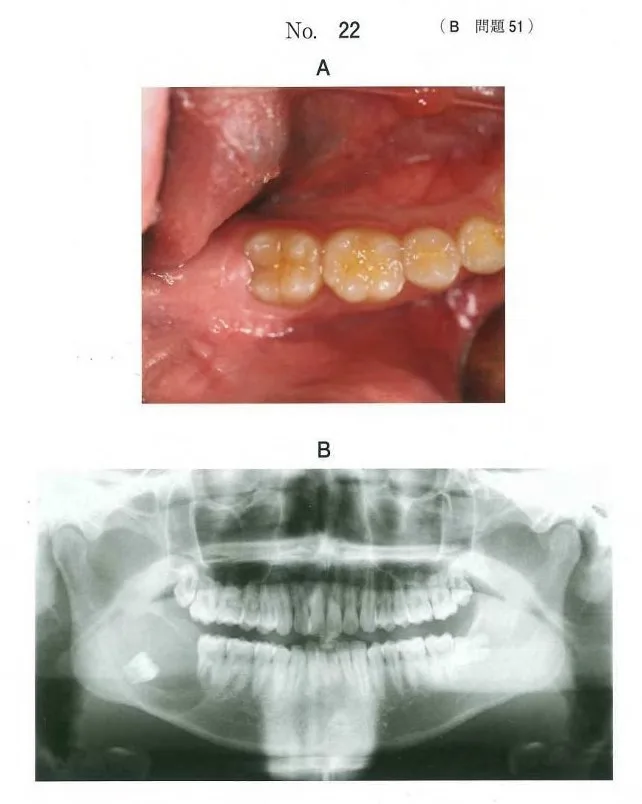

• 歯科医師国家試験 第115回 B51問題 | 歯科国試ドットコム